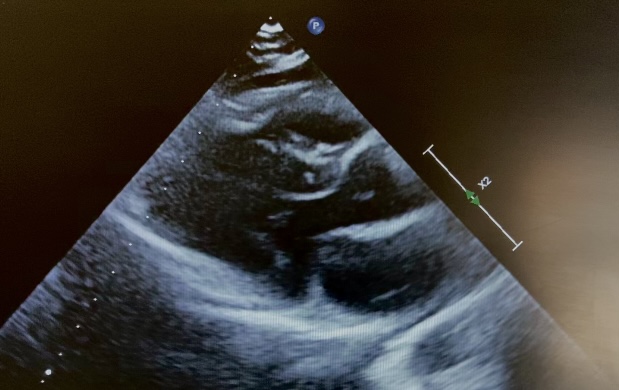

Introduction: Langerhans cell histiocytosis is a rare disease, more common in the pediatric age; the vinblastine–corticosteroid combination represents the first-line treatment. Cardiovascular effects of corticosteroids are generally mild; however, rare cases of obstructive hypertrophic cardiomyopathy have been described, mainly in the neonatal age. We report an exceptional case of reversible obstructive hypertrophic cardiomyopathy in a school-aged child. Clinical case: An 11-year-old boy started treatment for Langerhans cell histiocytosis according to the LCH-IV protocol with vinblastine and prednisone (1 mg/kg/day). After five weeks of therapy, an obstructive hypertrophic cardiomyopathy pattern was incidentally detected: parietal hypertrophy (IVS 10 mm, Z-score +2.8, figure 1) and dynamic left ventricular outflow tract obstruction (max PG 83 mmHg, figure 2) in an asymptomatic child. Over the following 3–4 weeks, during gradual steroid tapering, a complete regression of the condition was observed: echocardiography documented normalization of parietal thickness (IVS 8.5 mm, Z-score +1.1) and absence of outflow tract obstruction. Discussion and conclusions: obstructive hypertrophic cardiomyopathy represents a rare but clinically relevant complication of corticosteroid therapy in pediatric age. Most cases described in the literature involve neonates or infants exposed to high steroid doses, in whom myocardial hypertrophy appears related to the direct anabolic effect of glucocorticoids on the immature myocardium. In school-aged children this event is exceptional and poorly documented, particularly in the context of therapy for Langerhans cell histiocytosis. The reported case is peculiar due to the patient’s age, the absence of symptoms, and the diagnosis made during routine cardiologic surveillance. The close temporal correlation with the initiation of steroid therapy and the rapid and complete regression of the condition after prednisone reduction strongly support a pharmacological etiology. This case highlights the importance of maintaining a high level of clinical awareness and considering targeted cardiologic surveillance in pediatric patients undergoing steroid treatment, especially in cases of prolonged exposure or high doses.